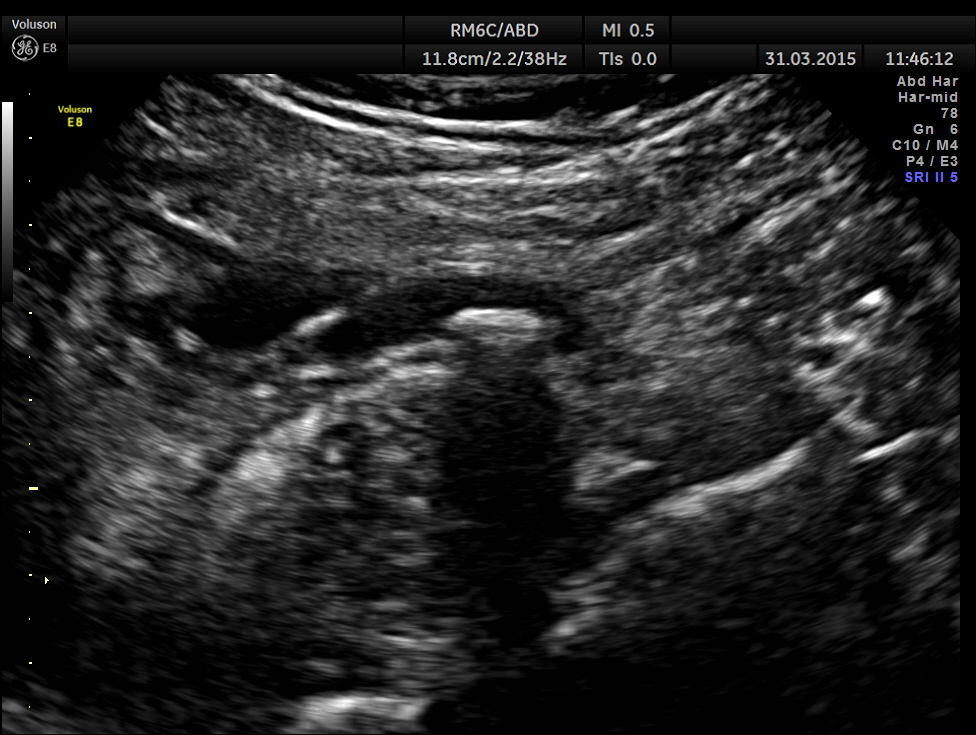

Ultrasound showed the following.

Scan ( with a regular abdominal probe ) over RIF shows an echogenic object with posterior acoustic shadowing within a dilated ” tube ” .

Colour Doppler shows vascularity of the wall . It was non pulsatile and non collapsible.

Now this looks more like an inflamed appendix with a prominent fecolith of size 11.4 mms , throwing a shadow.

The following pictures are with a high resolution probe.